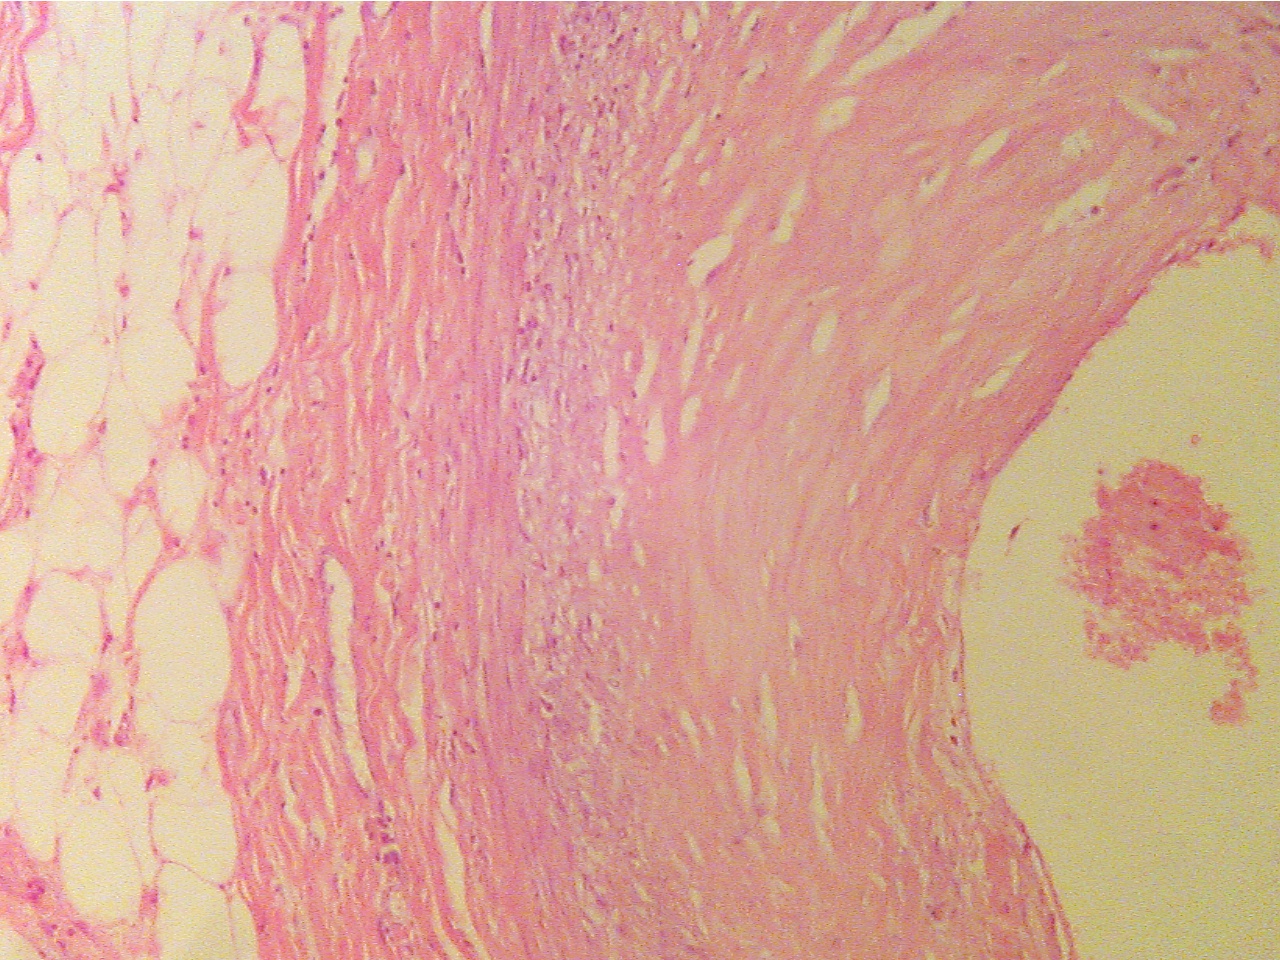

First observe a slide of an early atherosclerotic lesion (PH 813). The

pink, noncellular material in the intima of the coronary artery is the

atherosclerotic

plaque. This lesion has already reduced the lumen by about 20%. Now

observe one of the later atherosclerotic plaques (PH 804 or PH 814).

Early lesion

(40X1.0 - a1)

Normal artery wall at left, lumen in center,

lesion (thickened wall) at right.

Normal region (100X2.0 - a1)

Early lesion (100X2.0 - a2)

Layers are areolar tissue (left), externa (thick pink

Lumen at upper left, endothelium (thin layer),

collagen fibers),

smooth muscle (thick middle layer),

intima, fibrous plaque within intima, intima (darker

granular

tunica intima (thick granular layer),

endothelium

layer), smooth muscle (thick pink), externa (lower right)

(thin red layer), lumen at

right